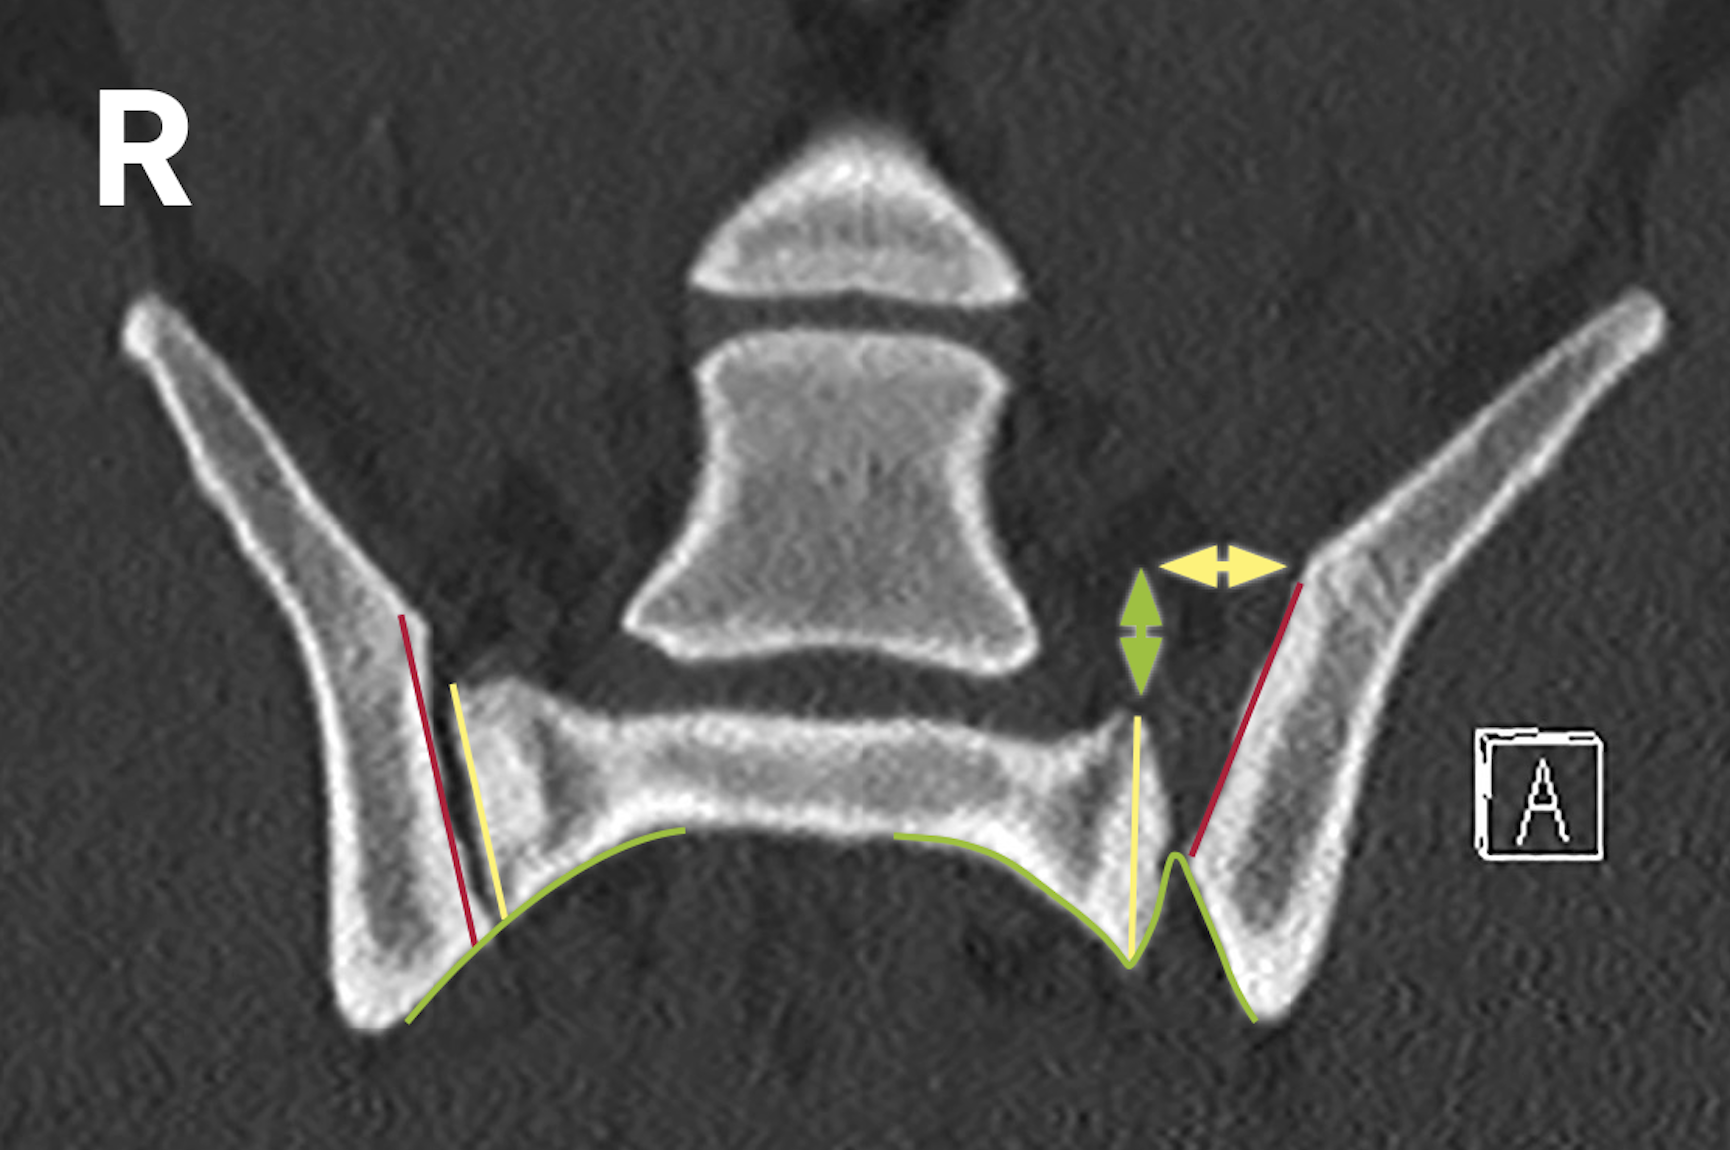

Der Befund ergibt eine iliosakrale Luxation bzw. Diastase. Die Stufe in den Konturen zeigt die Luxation des Darmbeins nach kranial (grün). Die Verbreiterung des Gelenkspalts zeigt die Dislokation des Darmbeins nach lateral (gelb).

• Leicht dislozierte Diastasen oder Sakrumfrakturen sind aufgrund von Überlagerungen beim Röntgen manchmal nicht zuverlässig zu sehen.

• In diagnostisch unklaren Fällen können komplementäre Röntgenbilder in Position 1 und 2 sowie die CT weiterhelfen.